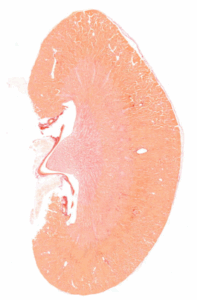

UUO Model of Kidney Fibrosis

The gold standard in Renal Fibrosis research – the Unilateral Ureteral Obstruction Model

Unlock the anti-fibrotic potential of your compounds with our Unilateral Ureteral Obstruction (UUO) model. Widely used for assessing renal fibrosis, UUO reproduces key pathological hallmarks of Chronic Kidney Disease, including interstitial fibrosis, tubular atrophy, and inflammatory cell infiltration.

Through precise ligation of one side of the ureter, we induce targeted disease pathology while minimizing procedural variability. Subsequently, the diseased kidney is divided into three sections, enabling thorough analysis across different modalities. From histopathological assessments to biochemical assays and gene expression profiling, our UUO model offers an efficient tool to explore renal fibrosis progression.